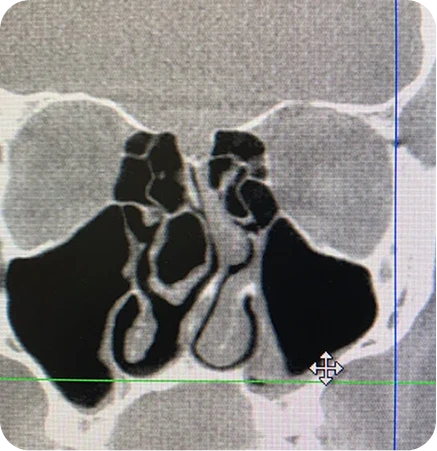

For example, swelling from chronic sinusitis, a deviated septum, enlarged turbinates, and nasal valve collapse could all be the cause. Fixing one of these things, but not the others, will not correct the problem. In this case, the answer would be balloon sinuplasty to fix the sinusitis, turbinate reduction, septoplasty, and nasal valve reconstruction.

At our Houston clinic, we take a personalized approach to diagnosing and treating nasal congestion, difficulty breathing, and other sinus conditions. Using advanced tools like the NOSE score test and nasal endoscopy, we carefully evaluate both nostrils to identify the underlying cause of your symptoms, whether it’s turbinate hypertrophy, nasal polyps, a deviated septum, or chronic sinusitis. Our team also assesses how structural issues or inflammation may pull outward on nasal passages, contributing to trouble sleeping, sinus pressure, or other symptoms.